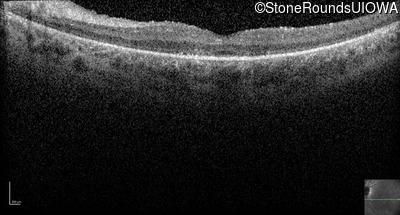

Optical Coherence Tomography - Left - 20/200 -2

Exemplar / OCT Stack